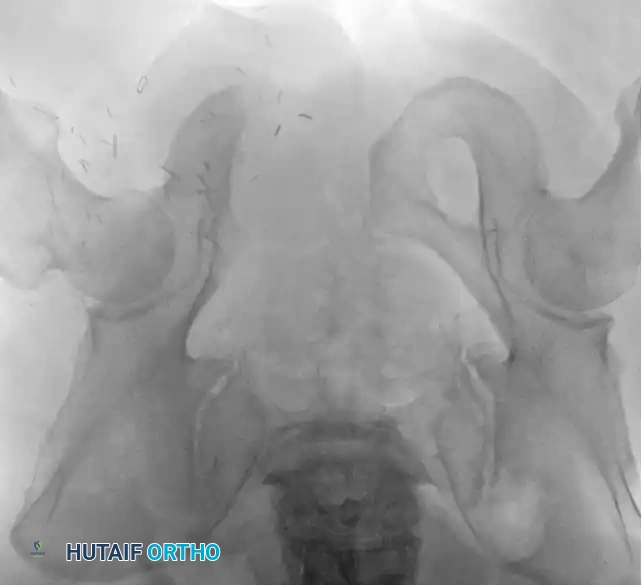

Intraoperative Imaging and Margin Assessment

Continuous intraoperative assessment using fluoroscopy and frozen section pathology is mandatory. The following images demonstrate various stages of complex upper extremity resections, allograft preparations, and prosthetic implantations across the humerus and elbow joint.